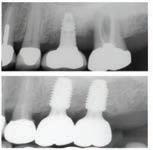

치주 질환, 방치하면 큰 문제로

치주 전문 치과에서의 치료가 중요한 이유 (치주 전문 및 종합 치과 - 밸리 가주 종합치과 제공)

치주 질환은 잇몸과 치아 주변 조직에 생기는

염증성 질환으로, 적절한 치료 없이 방치할 경

우 치아 손실을 비롯해 구강 건강에 심각한 영향을 미칠 수 있습니다.

잇몸 출혈, 입 냄새, 치아의 흔들림 등, 초기증상을 간과하면, 병이 진행되어 치아를

지탱하는 치조골까지 손상될 수 있습니다. 그렇기 때문에 치주 질환을 예방하고 치

료하는 치주 전문치과의 역할이 매우 중요합니다.

치주 질환의 가장 큰 원인은 구강위생 관리부족으로 인한 플라크와 치석의 축적입

니다. 이로 인해 잇몸이 염증을 일으키고, 심할 경우 잇몸조직이 손상되어 치아를 지

탱하는 뼈까지 영향을 미칩니다.

초기 단계인 치은염은 간단한 스케일링과 정기적인 관리로 치료할 수 있지만, 치주

염으로 발전한 경우에는 더 정교한 치료가 필요합니다. 치주 질환은 단순히 잇몸 문

제에 그치지 않고, 전신 건강에도 영향을 미칠 수 있습니다. 그렇기 때문에 정기적인 치과 방문과 예방적 관리는 필수적입니다.

치주 전문치과 가주종합치과에서는 최신 치료 기술과 경험으로 전문적인 진단과 개

별 맞춤형 치료를 통해 환자의 최상의 구강 건강을 위해 진료를 하고 있습니다. 잇

이곳은 치주 질환뿐만 아니라 일반적인 치과 치료, 치아교정, 미용 치과, 신경 치료, 임플란트 등 다양한 전문 분야를 포괄적으로 다루고 있으며, 특히 시니어 덴탈 프

로그램을 운영해 메디칼, 메디케어와 연계된 상담과 진료를 제공합니다.

Anthem, Astiva, Aetna, Clever Care, Liberty, Humana, United Healthcare등의 보험을 환영하며, 치과 치료가 필요한 시니어 환자들에게도 최적의 의료 서비스를 제공합니다.

밸리 가주 종합치과의 의료진은 각 분야에서 풍부한 경험을 쌓은 전문가들로 구성

되어 있습니다. 또한 밸리 가주 종합치과는 최신 장비와 세심한 진료를 통해 환자 들에게 무이자 할부 프로그램과 각종 PPO 보험을 환영하며, 경제적인 부담 없이 치 료를 받을 수 있는 환경을 제공합니다. 그리고 365일 24시간 전화 상담 서비스를 통 해 언제든지 환자들의 궁금증과 상담을 해결해 주고 있습니다. 멀리 LA까지 가실 필요 없이 가까운 밸리 가주 종합치과를 방문하세요. 상담 및 문의 : (818) 832-2828 | 17526 Chatsworth St. Granada Hills, CA 91344

몸출혈이나 치아의 흔들림 같은 초기증상이 나타난다면, 이를 절대 가볍게 넘기지 말고 즉시 치과를 방문하여 상담을 받는 것이 좋습니다. 밸리 지역에서 신뢰받는 치 과 밸리 가주 종합치과는 모든 치과 치료를 한곳에서 받을 수 있는 종합 치과로, 교정 전문의와 치주 전문의가 함께 환자의 구강 건강을 책임지고 있습니다.